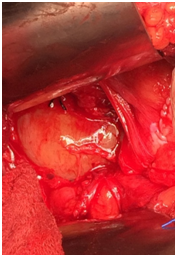

30 years old gentleman arrived with complaints of lower abdominal discomfort for 6 months with vague right iliac pain with normal gut and bladder habits. He experienced no other co-morbidities. Clinical examination findings were normal. Blood investigation was done within normal limits. Ultrasound abdomen showed a complex cyst with internal echoes and absence of vascularity in the right side of the pelvis. Contrast CT abdomen revealed non enhancing unilocular cystic mass on the right lateral pelvic wall.MRI, abdomen with gadolinium revealed T1 hypotenuse, T2/STIR heterointense enhancement within the lesion. Colonoscopy was normal. He underwent laparotomy under general anesthesia, through Pfannenstiel extra peritoneal approach mass lesion of size 8cm x 6 cm identified in the right pelvic region in the course of obturator nerve producing the compression over the lateral wall of the bladder without any infiltration of the bladder and bowel. It was arising from the nerve bundle, the lesion was well capsulated. It was highly vascular with blood supply from the branches of internal iliac arteries. The feeding arterial branch was ligated, outer capsule opened and an inner mass removed completely after leaving the capsule intact in view of nerve injury. Haemostasis achieved, postoperative period was uneventful. Histopathology revealed a mass of size 8x6.5x3.5cm section shows unencapsulated lesion comprised of spindle cells with wavy nuclei prominent myxoid stroma and scant collagen, conclusive of as Neurofibroma (Figures 1-4).

Figure 4 Shows intraoperative picture of mass with increased vascular supply.